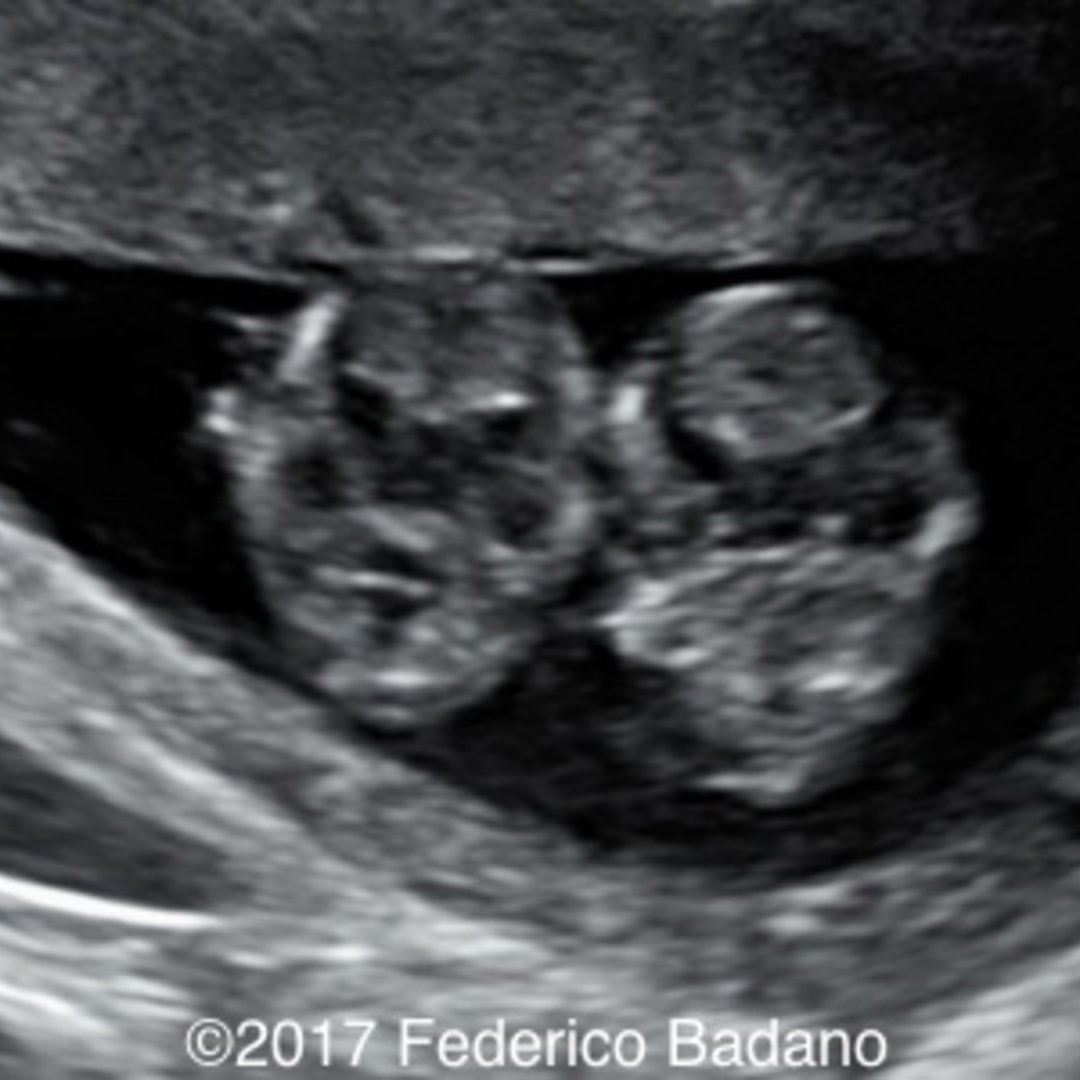

Figure 7 from Umbilical Cord Entanglement Diagnostic and Clinical What Is Cord Entanglement  Symptoms present in the baby shortly.   umbilical cord entanglement is the most common pathological condition among umbilical cord abnormalities [1],.  cord entanglement results from active fetal mobility and is facilitated by abundant amniotic fluid (especially if there is.  cord entanglement is defined as an umbilical cord that encircles the fetal body, neck, or extremities [1].  a. What Is Cord Entanglement.

Umbilical cord entanglement in monoamniotic twins Zollner 2012 What Is Cord Entanglement    umbilical cord entanglement is the most common pathological condition among umbilical cord abnormalities [1],.  cord entanglement is defined as an umbilical cord that encircles the fetal body, neck, or extremities [1].  umbilical cord entanglement in monoamniotic twins is a biologically plausible phenomenon that can be.  cord entanglement results from active fetal mobility and is facilitated by. What Is Cord Entanglement.